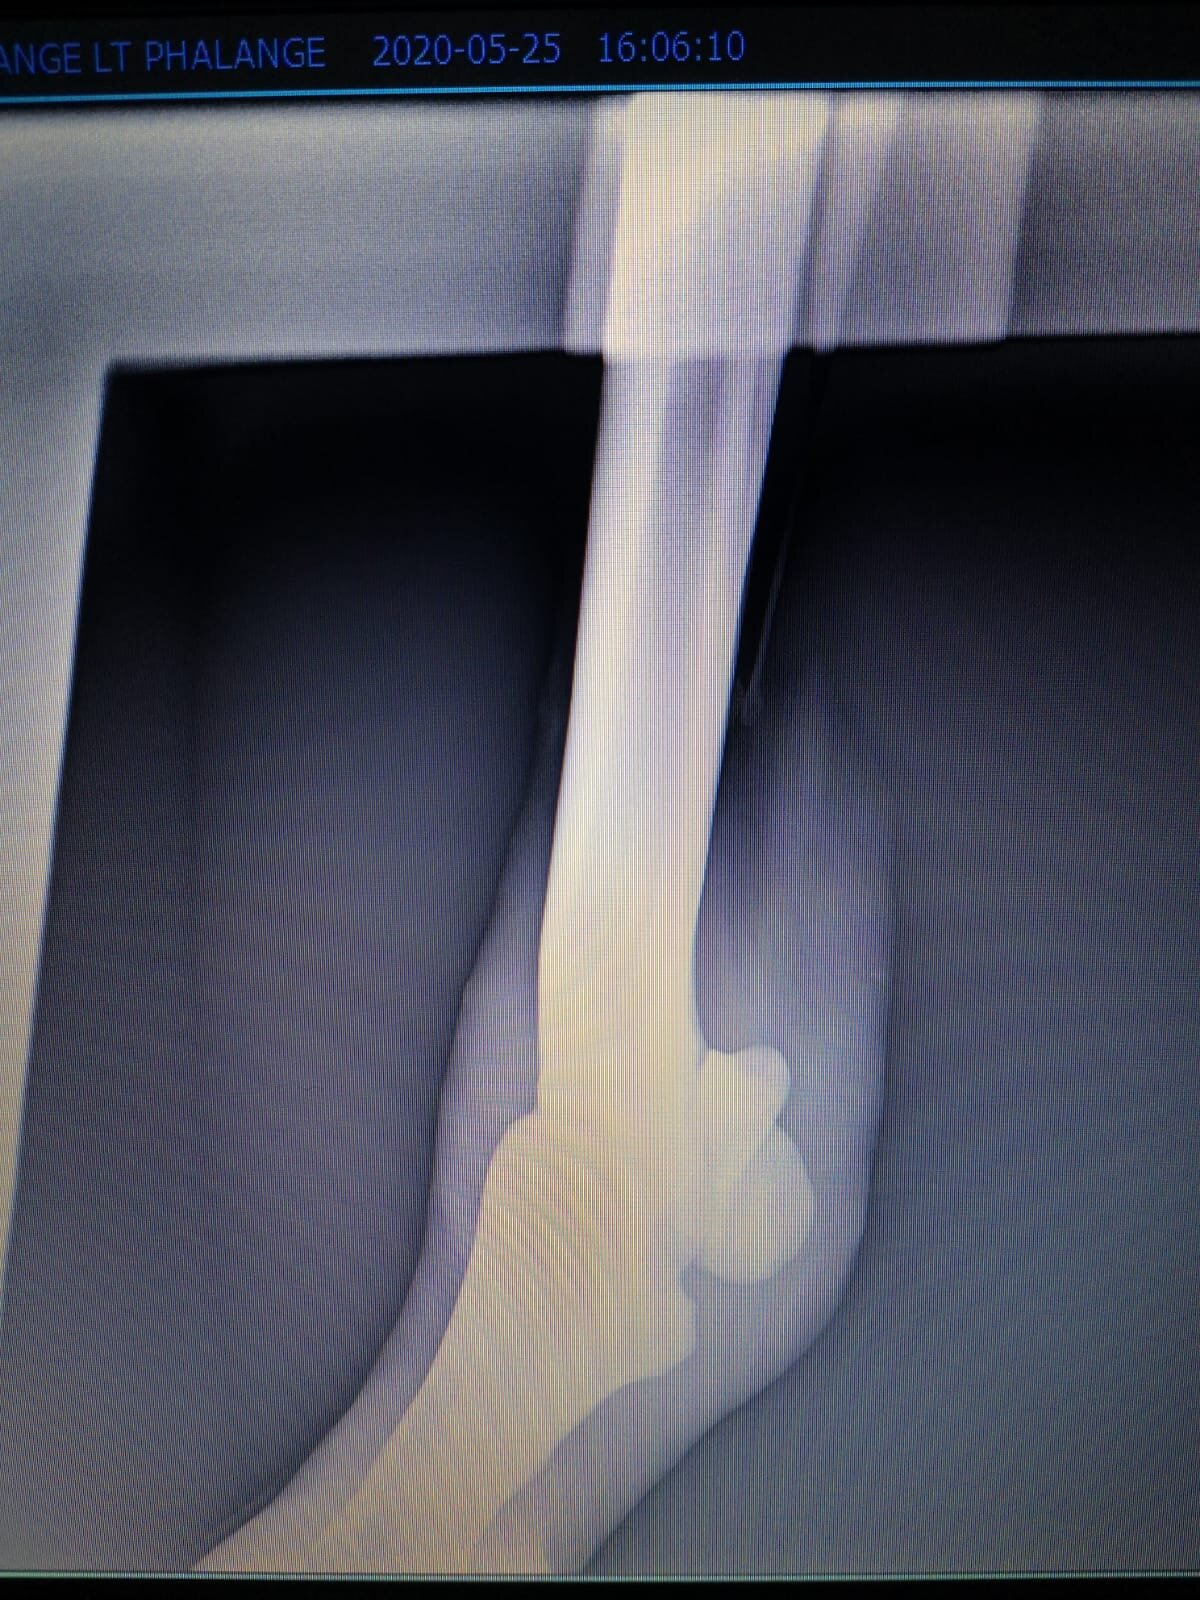

Salve volevo chiedervi qualche informazione in merce tò a un problema che ho avuto con la mia puledra. Qualche settimana fa mentre stavo lavorando alla corda è scivolata urtato l'arto posteriore sinistro. Arrivati in box ho messo dell'acqua a pressione perché si era gonfiato sia il nodello sia il pastorale. Già l'indomani l'arto era sgonfio ritornato normale, quindi ho continuato a lavorarla. Ma dopo qualche giorno di lavoro alla corda leggerissimo, al rientro in box ho notato che sia il nodello che il posturale gonfiavano nuovamente. Allora ho chiamato il veterinario che ha detto che la cavalla aveva una lussazione e mi ha insegnato come cura una fasciatura con della creta per 24h per cinque giorni e un antinfiammatorio. Dopo un paio di giorni la fasciatura ha fatto come delle vesciche e il gonfiore è aumentato dal pastorale alla garra. Abbiamo chiamato un altro veterinario abbiamo fatto vedere anche a lui la cavalla e diceva che poteva essere la frattura del ditino, ma si dovevano fare le lastre per essere sicuri. Ora abbiamo fatto le lastre e il radiologo dice che c'è dell'infiammazione ma non c'è niente di grave. Il veterinario,viste le lastre dice che deve essere operata. Allora abbiamo consultato un'altro veterinario che dice che la cavalla non ha assolutamente niente. Ora io vi allego le radiografie, datemi un vostro parere perché non só più cosa fare. Grazie

IMG-20200525-WA0010.jpg

IMG-20200525-WA0013.jpg

IMG-20200525-WA0014.jpg

IMG-20200525-WA0011.jpg

IMG-20200525-WA0012.jpg

IMG-20200525-WA0006.jpg

IMG-20200525-WA0017.jpg

IMG-20200525-WA0007.jpg

IMG-20200525-WA0018.jpg

IMG-20200525-WA0015.jpg

IMG-20200525-WA0005.jpg

IMG-20200525-WA0016.jpg

IMG-20200525-WA0008.jpg

IMG-20200525-WA0009.jpg